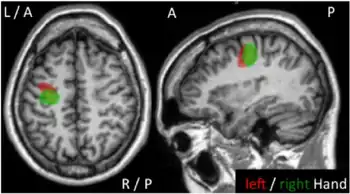

Axial, and sagittal MR images of individual with recurrent motor seizures, epilepsia partialis continua, of the left hand since the age of two